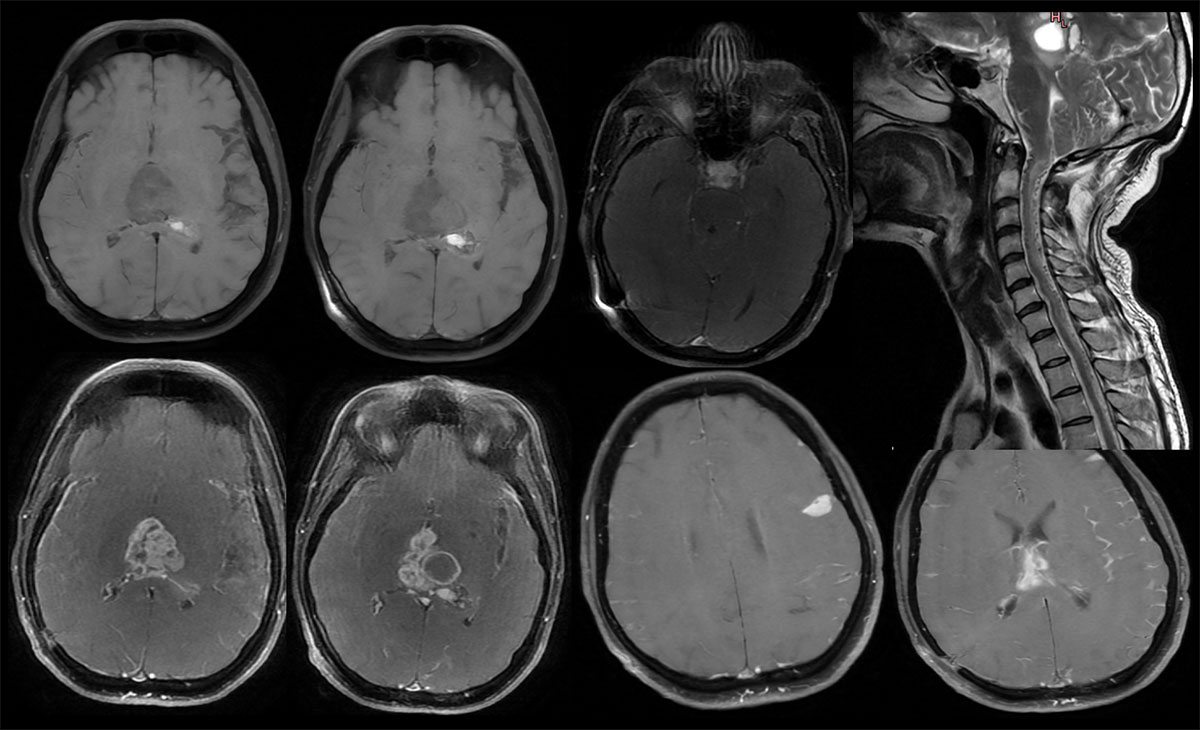

Diagnosis: Synchronous Pineal and Sellar-suprasellar Diffuse Midline Glioma, H3 K27 M Mutant CNS WHO Grade 4 with leptomeningeal and drop metastases.

MRI:

- Heterogeneous, multiloculated solid-cystic lesion with calcifications and haemorrhage in pineal region causing mass effect of brainstem, the solid component shows intense enhancement and the cystic areas show peripheral enhancement.

- Similar solid lesion seen in sellar-suprasellar region, shows intense contrast enhancement.

- Multifocal areas of nodular and smooth leptomeningeal enhancement predominantly along the cerebral hemispheres (L>R).

- There is leptomeningeal enhancement along the visualised cervical cord – leptomeningeal drop metastasis.

Incidental finding: multiple flow voids seen along the cervical and thoracic cord, no nidus and oedematous cord signal changes secondary to venous congestion – dural AV fistula.